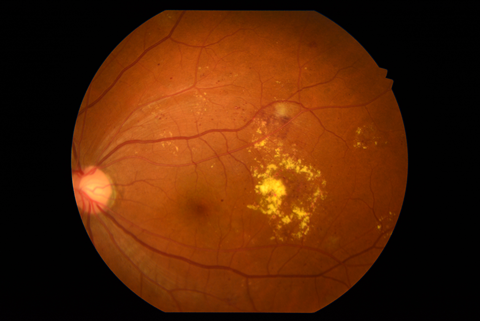

1.単純糖尿病網膜症

| 病期 | 症状 | 治療法 |

|---|---|---|

| 初期の網膜症 | 高血糖の影響から毛細血管の血管壁が障害され、血管に瘤ができたり、血管壁から血液や血漿成分がしみ出たりすることによって、点状出血や硬性白斑(脂肪やタンパク質の漏出)が生じます。 | この段階では血糖治療、高血圧治療が非常に大切になります。しかし、この段階でも黄斑浮腫が生じている場合には、レーザー治療(網膜光凝固術)や抗VEGF療法の適応になる場合もあります。 |

硬性白斑 |